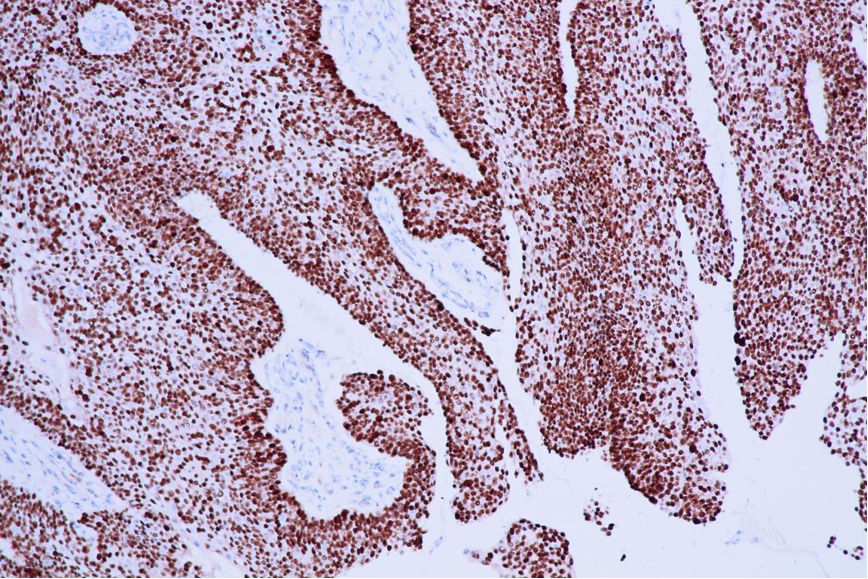

免疫组化结果:AE1/AE3(+)、CK5/6(+)、p40(+)、p63(+)、CK8(部分+)、CK19(+)、EMA(部分+)、AR(+)、SMARCA4(+)、SMARCB1(+)、Ki-67增殖指数为5%~20%

GCDFP-15(-)、p16(局灶+)、CK7(局灶+)、p53(野生型)、CK20(-)、vimentin(-)、S-100(-)、NUT-1(-)

AFF2 +

p63(+)、p40(+)、NUT(-)、p16(灶+或-)

抗AFF2末端抗体具有高度的敏感性和特异性,若30%的细胞呈现中~强的核阳性,对DEK-AFF2癌的诊断具有重要价值